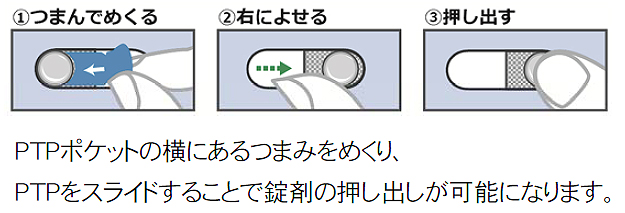

お薬の小児誤飲防止パッケージ スライド台紙ptp 株式会社カナエ

お薬の小児誤飲防止パッケージ スライド台紙ptp 株式会社カナエ